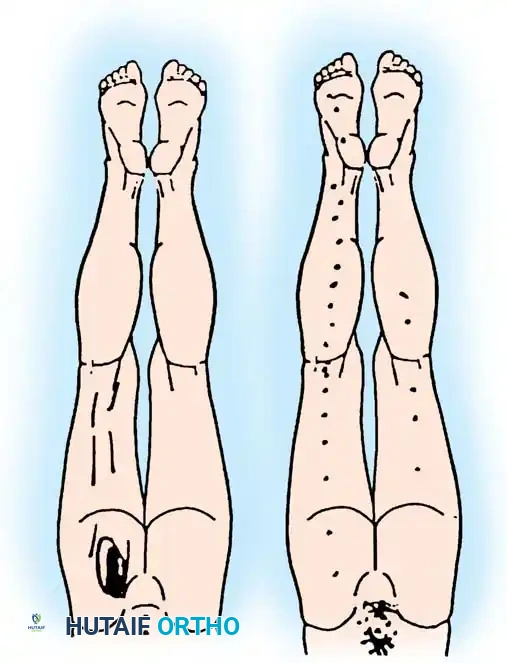

When discrete, well-controlled injection techniques are directed at specific targets in and around the spine, grading the degree of pain before and after the injection is the definitive method for localizing the pain generator.

The patient must be instructed to grade their pain on a standardized 0-to-10 scale prior to the procedure and at specific intervals post-injection.

Diagnostic Threshold: If a selective spinal injection performed under strict fluoroscopic control results in a 50% or greater decrease in the level of pain (corresponding to the pharmacological duration of the anesthetic agent used), the targeted anatomical area is presumed to be the primary pain generator.

* Prognostic Value: Patients with acute back and leg pain (< 3 months duration) respond significantly better to epidural corticosteroids. Furthermore, patients who achieve substantial (even if temporary) relief of leg pain from a well-placed transforaminal injection are highly likely to benefit from definitive surgical decompression. Conversely, patients who fail to respond and have endured radicular pain for >12 months are statistically unlikely to benefit from surgery.

- Neurological Assessment: Evaluate motor and sensory function in the extremities. Transient weakness is common due to the local anesthetic, but profound motor block requires observation until resolution.

- Pain Diary Completion: The patient must complete the post-injection pain diary (Box 39-2) at 30 minutes, 2 hours, and 6 hours post-procedure. This data is the primary outcome measure for surgical planning.